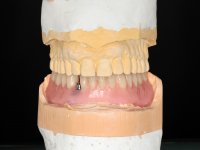

Two dental implants were planned in the CBCT scan, in the area of the inferior canines. The dental extractions were performed and, simultaneously, the alveolar crest was flattened and the implants were placed. Three issues were considered while implant placement: parallelism of the axis, same height of the implant’s neck, and same position in the coronal plan. This 3D insertion is essential to have a good retention of the overdenture in the future. Patient’s removable denture was fixed in the dental lab, to include the extracted teeth, and a soft-tissue relining was done over the healing abutments. After the osseo-integration period, a first impression was done with an open-tray and a doble-mix technique. This dental impression allowed the production of screwed wax-rims and an individual tray for a functional impression. A second impression, final, was done with an individual tray with a monophasic silicone. The occlusal wax-rims were correct in the mouth according to the full denture guidelines. Special care was taken with the occlusal vertical dimension and the support in the soft-tissues. A silicone bite registration material was used to better defined the intermaxillary relations. Teeth set-up was done in the dental lab with the selected tooth color. Due to the fact that the base was screwed to the dental implants, the teeth set-up was functionally evaluated in the mouth. Another silicone bite registration material was used to allow final occlusal adjustments. Finally, the locators were screwed and the retention nylons were selected according to the patient needs.